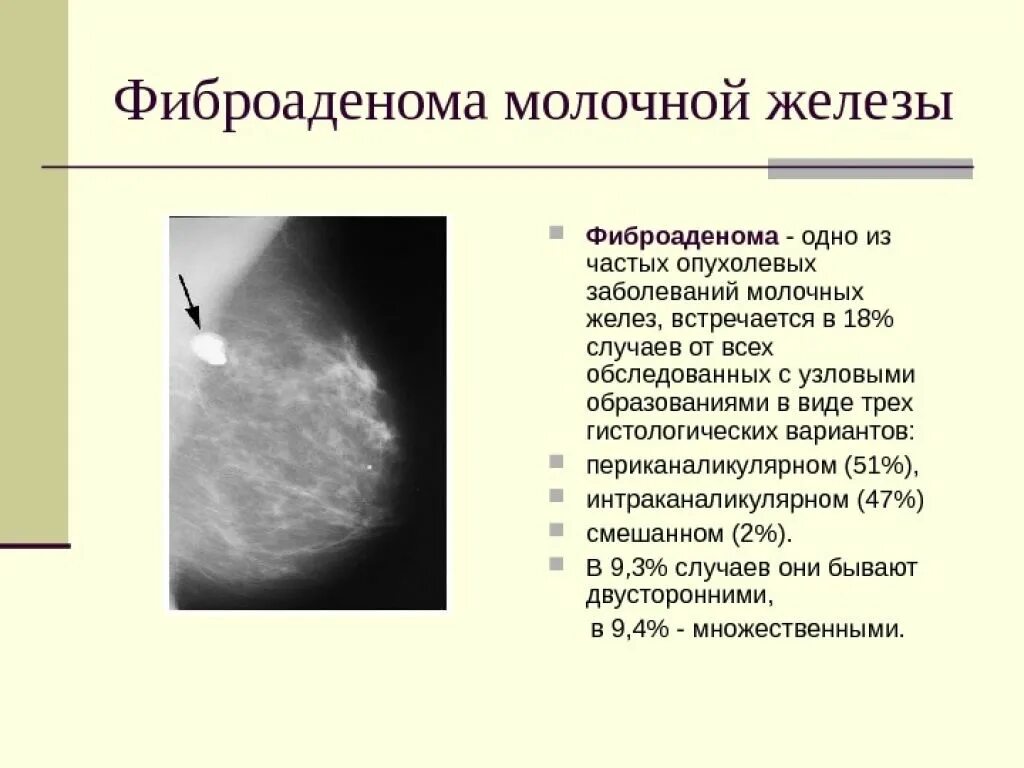

Новообразование в головном мозге. Презентация опухоль мозга. Опухоли головного мозга презентация. Злокачественная фиброаденома молочной железы. Фиброаденома молочной железы Размеры для операции. Фиброаденома молочной железы маммография. Листовидная опухоль гистология.

Злокачественная фиброаденома молочной железы. Фиброаденома молочной железы Размеры для операции. Фиброаденома молочной железы маммография. Листовидная опухоль гистология. Доброкачественная опухоль. Доброкачественныеопкхоли. Клетки, образующие доброкачественную опухоль:. Строение доброкачественной опухоли.

Подчелюстная слюнная железа на рентгене. Сиалография слюнных желез. Рентгенография слюнных желез. Контрастная сиалография слюнных желез. Фиброаденома молочной железы дифференциальный диагноз. Новообразование молочной железы фиброаденома. Диф диагноз фиброаденомы молочной железы. Фиброаденома молочной железы 30мм-37мм.

Фиброаденома молочной железы дифференциальный диагноз. Новообразование молочной железы фиброаденома. Диф диагноз фиброаденомы молочной железы. Фиброаденома молочной железы 30мм-37мм. Диагностические критерии глиомы головного мозга. Особенности опухолей лобной доли. Клиника опухоли затылочной доли головного мозга. Симптомы, характерные для опухолей лобной доли.